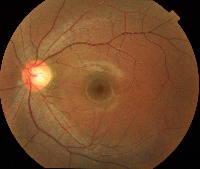

Classes (69)

0.0.Normal

0.1.Tessellated fundus

0.2.Large optic cup

0.3.DR1

1.0.DR2

1.1.DR3

10.0.Possible glaucoma

10.1.Optic atrophy

11.Severe hypertensive retinopathy

12.Disc swelling and elevation

13.Dragged Disc

14.Congenital disc abnormality

15.0.Retinitis pigmentosa

16

17

18

19

2

2.0.BRVO

2.1.CRVO

3.RAO

4.Rhegmatogenous RD

5.0.CSCR

5.1.VKH disease

6.Maculopathy

7.ERM

8.MH

9.Pathological myopia